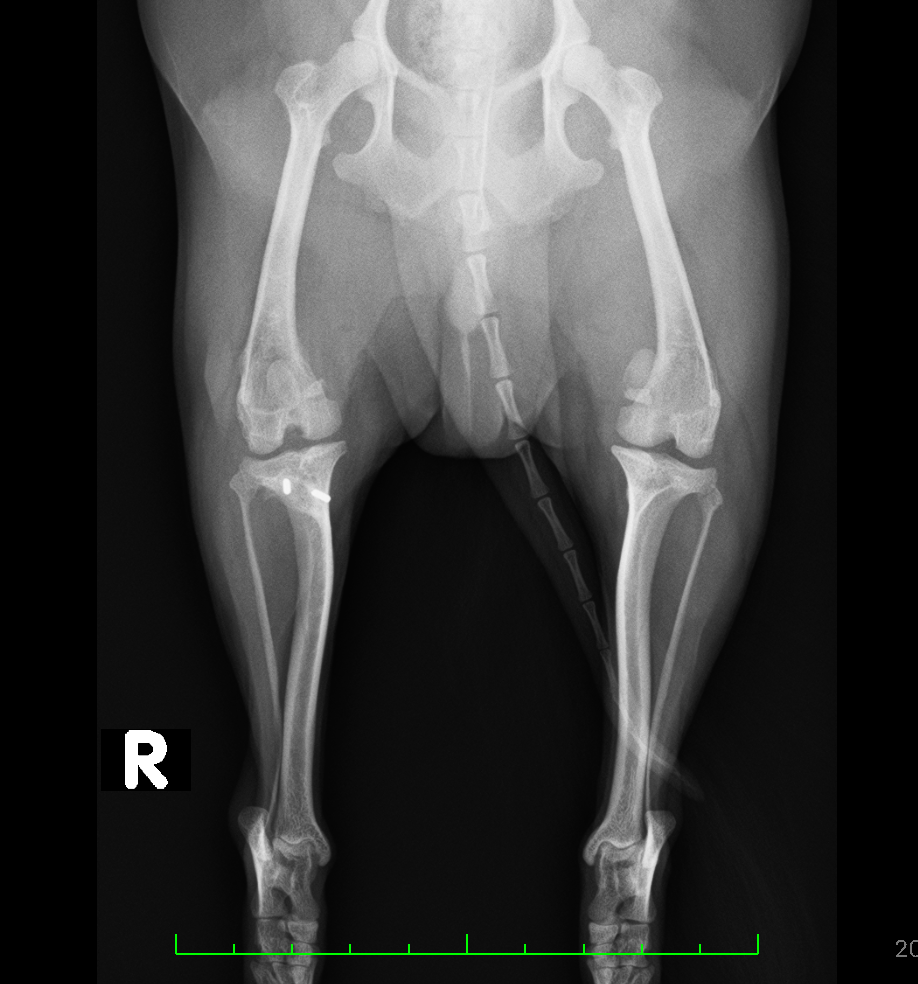

左右膝蓋骨内方脱臼、右前十字靭帯断裂

after